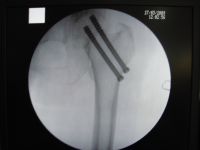

2.内固定:目前有条件的医院在电视X光机的配合下,采用闭合复位内固定,如无X光机设备,亦可采用开放复位内固定。在内固定术之前先行手法复位,证实骨折断端解剖复位后再行内固定术。内固定的形式很多,归纳约有以下几种类型:①Smith-Petersen三刃钉内固定:自1929年Smith-Petersen首次创用三刃钉以来,使股骨颈骨折的疗效显著提高,至今仍为常用的内固定方法之一。②滑动式内固定:现有各种不同式样的压缩钉或针。压缩钉或针可在套筒内滑动,当骨折线两侧有吸收时,钉向套筒内滑动缩短以保持骨折端密切接触,早期承重更利于骨折端的嵌插。③加压式内固定:此种内固定物带有压缩装置,能使骨折端互相嵌紧以利愈合。常用的有Charnley带有弹簧的压缩螺丝钉和Siffert使用的螺丝栓(Corkscrew Bolt)等。④多针(或钉)内固定:根据股骨上端骨结构和生物力学原则分别插入2~4根螺丝钉或钢钉,不但固定牢靠,而且可减少对股骨头的损伤。如Moore或Hagia针等。总之,内固定形式多种多样。